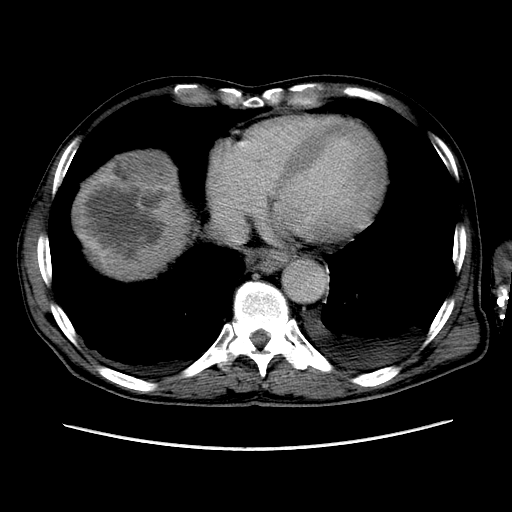

Печень. Процесс в средостении, бр.пол., забр.пр-ве. МСКТ.

Здравствуйте, коллеги! Мужчина около 70 лет. Жалобы: слабость, утомляемость около 3х месяцев, чувство тяжести на желудке после еды. Анамнез: онко не было. С вышеописанными жалобами обратился ко врачу, сделали ФГЭДС - признаки гастродуоденита, по биопсии - N. В течение 2х последних недель существенно похудел и начал желтеть. Выполнена МСКТ

Вероятно ГЦР, со всеми последствиями.

А как насчет холангиокарциномы с тромбозом воротной вены и мтс в средостение, лимфоузлы брюшной полости и забрюшинного пр-ва?

Я - за.

Внимательно пересмотрел, признаков характерных для ГЦР не нашел (кроме тромбоза). Согласен с холангиокарциномой, ещё бы отсроченную фазу, для печени минут через 12-15 .

Для ГЦР характерно

1. Гиперденсивность, в артериальную фазу  всей опухолевой массы (опухоль хорошо васкуляризирована)

2. Гиподенсивность, в портальную фазу (быстрое вымивание, опять же обусловлено васкуляризацией)

3.Тромбоз портальной вены.

Для холангиокарциномы характерно гиперденсивность, в отсроченную фазу, за счет аффинитета к контрастному веществу.